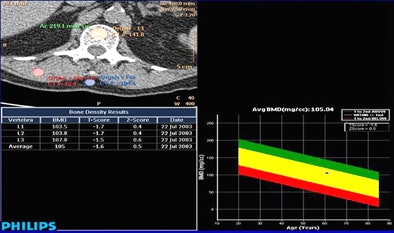

| Results (top) show mean scores for DEXA and CT-based bone mineral density analysis. Graph (below) demonstrates excellent correlation between derived bone mineral density and T-scores from CTC datasets with DEXA. There was excellent interobserver agreement between the two readers (bottom image) despite their having completed only a short training session on the BMAP software. |